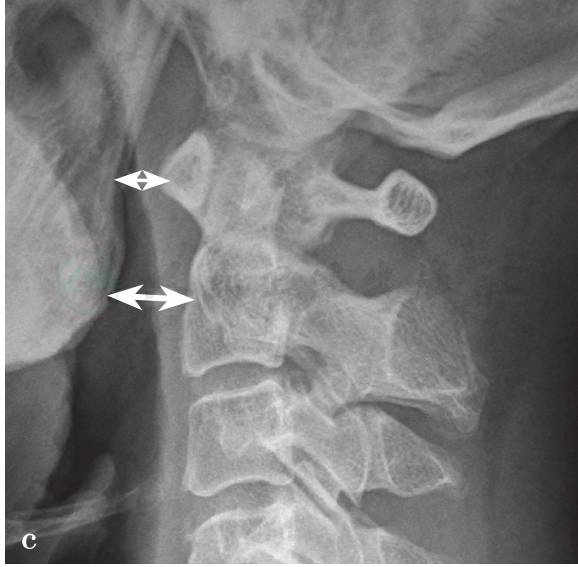

(3)Dublin法:

测量寰椎前结节和枢椎体至下颌骨后面皮质骨的距离,正常值分别为5mm 和10mm,超过此值为异常。由于双侧下颌骨后面的皮质骨影像受头部旋转体位的影响太大,所以该测量结果的可靠性低,对后脱位的准确性则更低(图4c)。

图4

a.寰枕关节脱位X线测量方法(BDT法);b.寰枕关节脱位X线测量方法(Power法);c.寰枕关节脱位X线测量方法(Dublin法);d.寰枕关节脱位X线测量方法(Kaufman法);e.寰枕关节脱位X线测量方法(X线法);f.寰枕关节脱位X线测量方法(BAI-BDI法)